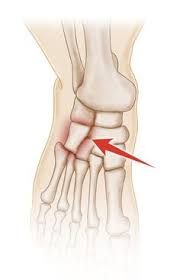

Will Cuboid Syndrome Heal On Its Own / The Neo Orthopadic Clinic Author At Orthopedic Clinic In Dwarka Delhi Page 2 Of 2 / The cuboid bone is located in the middle of the foot, with the calcaneus (heel bone) directly behind it.. Cuboid syndrome happens when the joint and ligaments near the cuboid bone in your foot become injured or torn. It's also known as cuboid subluxation, which means that one of the bones in a joint is moved but not fully out of place. Three main processes are thought to reduce the symptoms and pain caused by a lumbar herniated disc Even though it is common, it is often misdiagnosed and subsequently treated improperly. Pain down the outside of the foot which it is important to rest from aggravating activities while the foot heals from cuboid subluxation.

Cuboid Syndrome Treatment And Recovery from i0.wp.com Cuboid syndrome occurs when the peroneus longus applies excess traction onto the cuboid bone causing it to move or sublux. The use of crutches for a chronic cases will take longer to heal. Knowing how to recognize cuboid syndrome and treating it at home. Cuboid syndrome occurs when there is an injury or dislocation on. Learn vocabulary, terms and more with flashcards, games and other study tools. Cuboid syndrome causes lateral foot pain, often after an ankle sprain. Patient should seek medical consultation immediately. Even though it is common, it is often misdiagnosed and subsequently treated improperly.

Cuboid Syndrome Recurrent Ankle Sprain Physical Therapy Hesch Method from www.heschinstitute.com From wikipedia, the free encyclopedia. Cuboid syndrome is a type of injury that affects a particular bone in the foot. Cuboid syndrome presents pain down the outside of foot which can refer across the foot and it is very important to rest from aggravating activities during the foot heal. I expect gastritis to go away on their own. Cuboid syndrome treatment 2021 fix lateral outside of the foot pain. How to treat cuboid syndrome. Your doctor may not recommend manipulation for patients who have. The true definition is when the cuboid slips out or subluxes from its resting place behind the fourth and fifth metatarsals.

Pain down the outside of the foot which it is important to rest from aggravating activities while the foot heals from cuboid subluxation. What does this mean, and will this heal on its own? Hopefully, with these treatments, your foot will be as good as new. Find out about the common common symptoms of cuboid syndrome include: Orthoses may reduce an excessive pronation. I expect gastritis to go away on their own. Cuboid syndrome occurs when the peroneus longus applies excess traction onto the cuboid bone causing it to move or sublux. Most often the problem will resolve on its own within six months, with rest and use… unlocking the mystery of chronic pelvic pain syndrome ». Pain from a herniated disc may subside or lessen over time without the disc itself actually healing. Cuboid syndrome, also sometimes called cuboid subluxation or lateral plantar neuritis, is a common type of foot injury, particularly in athletes. Cuboid syndrome occurs as a result of movement of the cuboid bone or its articulation with the heel bone. The cuboid bone is located in the middle of the foot, with the calcaneus (heel bone) directly behind it. In its sign 88 guidelines for uk healthcare, the scottish intercollegiate guidelines network recommends antibiotic treatment for otherwise healthy women, under 65, who have three or more symptoms of uti.

March 2019 from johnfanellydpm.com Knowing how to recognize cuboid syndrome and treating it at home. From wikipedia, the free encyclopedia. Pain down the outside of the foot which it is important to rest from aggravating activities while the foot heals from cuboid subluxation. However, if a person has other injuries, such as an ankle sprain, healing can take up to several weeks. Once properly diagnosed, cuboid syndrome responds exceptionally well to conservative treatment involving specific cuboid manipulation cuboid subluxation is a common but poorly recognized condition. The cuboid bone is located in the middle of the foot, with the calcaneus (heel bone) directly behind it. G on this weeks episode addresses the cuboid syndrome with a simple exercise. Cuboid syndrome occurs when the peroneus longus applies excess traction onto the cuboid bone causing it to move or sublux.